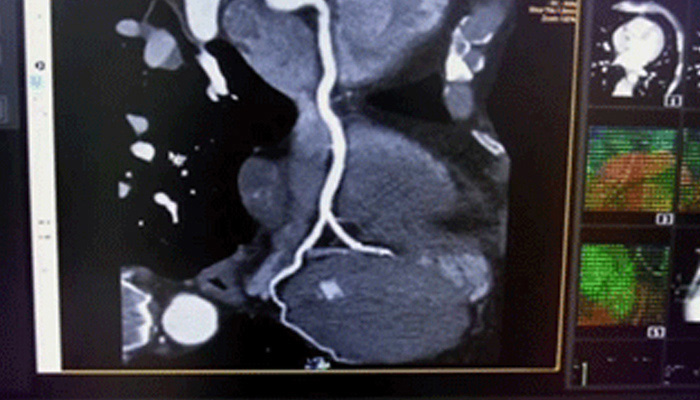

تشهد حاليًا خيارات العلاج التي لا تتطلب سوى تدخل جراحي محدود في القلب والأوعية الدموية انتشارًا ملحوظًا. ولقد ساهمت التطورات الأخيرة في مجالات التشخيص والتوجيه بالصور المباشرة Live Image Guidance والمعلوماتية في جعل هذا الأمر ممكنًا. بالتعاون مع أشهر أطباء أمراض القلب، ابتكرنا حلولاً تساهم في منح المرضى الفرصة لتغيير حياتهم. فهذه الحلول تساعد في تسريع سير العمل وزيادة فعالية الطاقم الطبي وتوفير أفكار سريرية.

تعلّم كيف تستطيع الحلول التي ابتكرناها في مجال طب القلب مساعدة مؤسستك